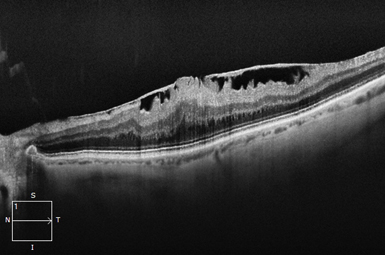

Macular Hole

A Macular Hole creates a blank space in the central “film of your camera”. Surgical repair is typically highly successful.

Image courtesy of Carl Zeiss Meditec, Inc.